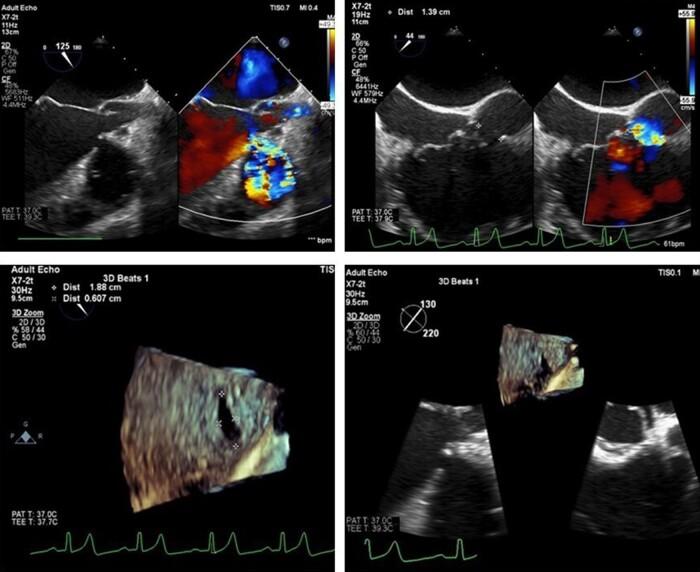

A 34-year-old male with known VSD was referred for transcatheter closure after failed attempts in other hospital. Patient had been diagnosed with VSD at a young age, but he was lost to follow-up. He presented with shortness of breath due to heart failure and pulmonary hypertension. The initial measurement of the defect was 6-7 mm by transthoracic echocardiography (TTE), transoesophageal echocardiography (TEE), and LV angiography. However, re-measurement using TEE and 3D echocardiography revealed that the VSD is oval with diameters of 18 mm × 6 mm. Initially, device No. 12/14 was used, but it was dislodged on two attempts. The operator then decided to upsize the device size to No. 16/18 that was successful. The patient's condition was good, and 6 months follow-up after the procedure showed good outcomes without any residual defect or arrhythmia.

In this study, we would like to highlight the rarity of large oval pmVSD that almost failed to be closed with the conventional measurement with echocardiography and fluoroscopy. Transoesophageal echocardiography especially 3D can be the new modality of choice that might be superior to fluoroscopy to decide the right device size in some cases such as oval-shaped pmVSD.